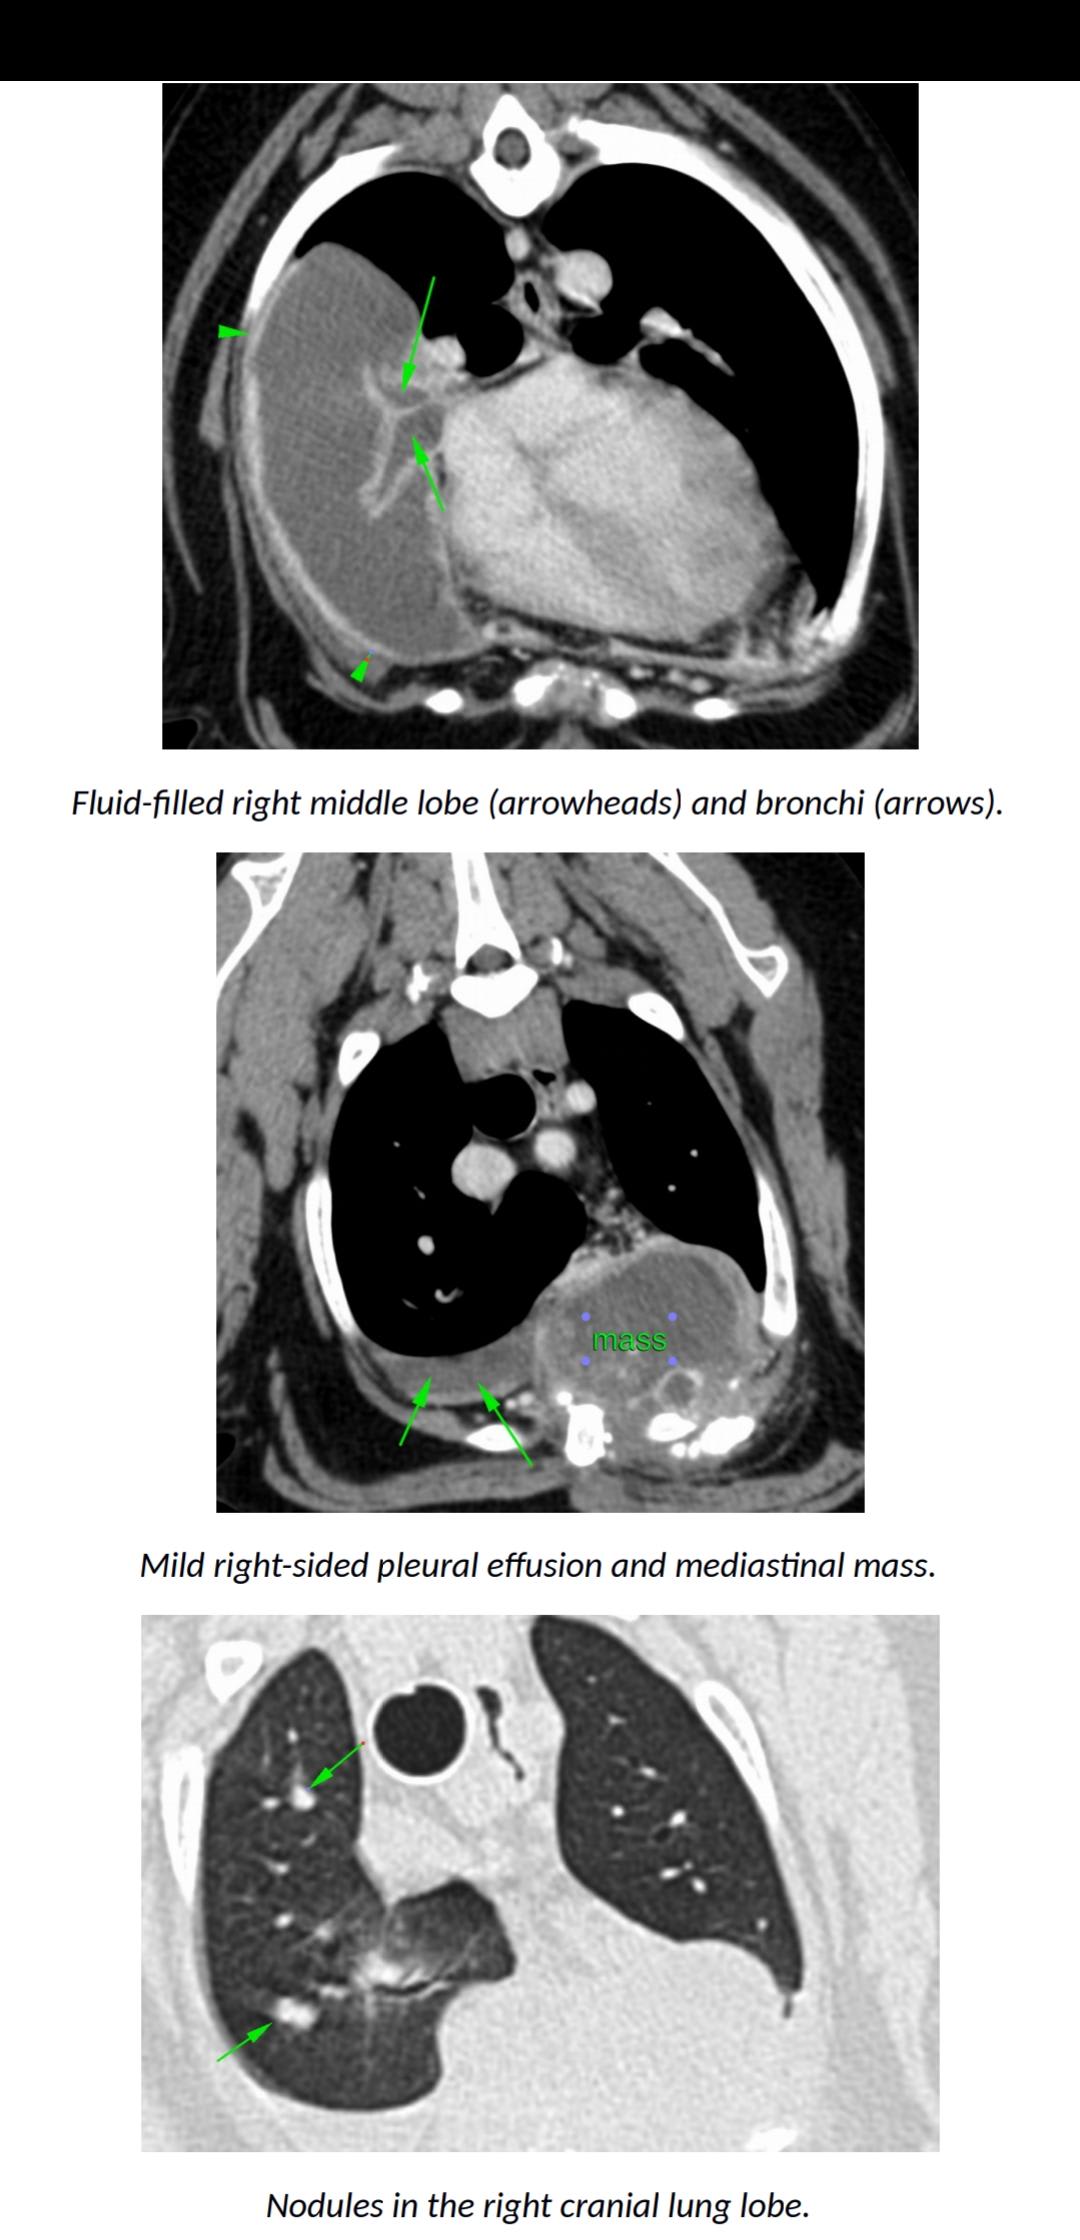

Hello. Yogi has this mass on his chest with nodules in his lung lobes and liver. He is however acting completely normal, going on walks, eating and in no apparent discomfort. He subsequently isn't currently on any medications. Is this normal? And should we expect him to go downhill soon/in the near future? Should this mass be causing him discomfort? He is breathing fine and doesn't seem to have his initial cough anymore except when overly exerting himself. Many thanks for your time

Thank you for submitting your question regarding Yogi. I am sorry to hear of his recent diagnosis. It is wonderful that he is still feeling well. I do not suspect this will be the case for long, as the mass and fluid will ultimately interfere with his ability to breathe. If treatment is not possible, it will continue to grow. I would suspect this to happen within 1-3 months. You can consider pain medication if his attitude or appetite changes. His veterinarian can prescribe something for him. In the meantime, enjoy all of your time with him.

Thank you for submitting your question regarding Yogi. How frustrating to not have any definitive answers regarding his condition. I am happy to hear that he is still doing well for you at home though. Unfortunately, regardless of the exact cause of his lesions, I suspect that he will begin to deteriorate. The lesions appear extensive and have the possibility to ultimately interfere with his breathing. I encourage you to enjoy him and make as many memories with him as possible. I have had some families created a bucket list of things to do with an aging pet. Best of luck.